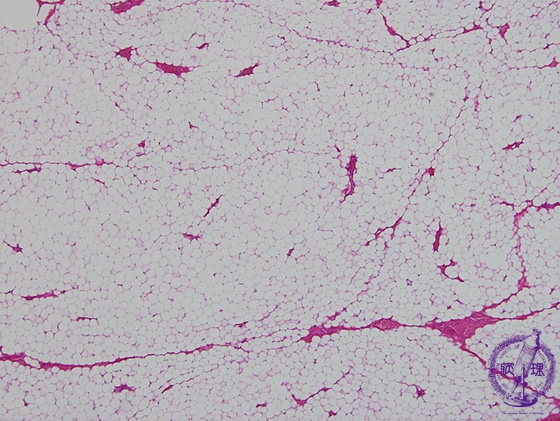

Microscopic findings (H.E. low power view): Lipoma composed of mature adipose tissue, indistinguishable from normal adipose tissue with light microscopy.